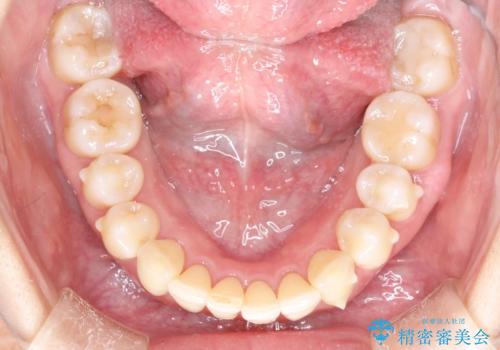

- 以前矯正をしていたが、わずかに後戻りをしてしまったのを主訴に来院されました。

装置はなるべくつけたくないとのことで、インビザラインにて治療することとなりました。

後戻りがわずかな場合は、期間も短くて済む場合があります。